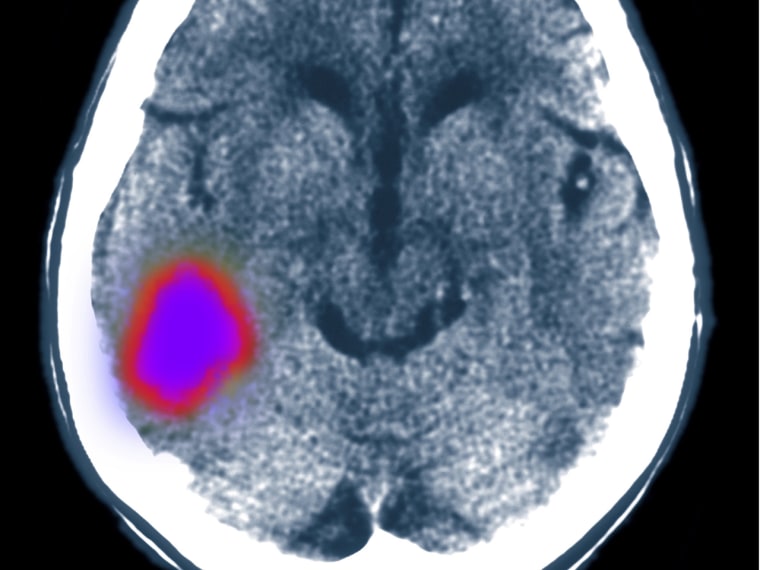

It may not be the best time to point this out, what with the looming stress of the holidays, but new research finds that all that anxiety you feel now and the rest of the year — well, it just might give you a stroke.

The problem, experts say, is that chronic anxiety can lead to a set of biochemical reactions that flood the body with a stress hormone, cortisol, and activate what’s known as the hypothalamic-pituitary-adrenal or HPA axis. That’s the system of feedback involving the hypothalamus, pituitary gland and the adrenal glands, which work together to regulate stress and other bodily functions.

When that activation is intense or prolonged, it can impair the vascular system, including the blood vessels in the brain, increasing likelihood of a stroke.